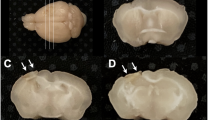

Ischemic stroke produced a significant atrophy at 5w in the injured hemisphere compared to the contralateral one. Quantification of brain atrophy showed no significant difference between tMCAo hBM-MSC and tMCAo PBS mice at this time point (Fig. 4A).

hBM-MSC promote neuronal survival in the perilesional area. (A) Stroke induces a similar atrophy in tMCAo hBM-MSC and tMCAo PBS mice 5w post-injury. (B) Representative micrograph shows typical brain atrophy and displays the ROI selected for histopathological analyses. Quantification of neuronal death in perilesional cortex (red box) indicates a neuronal rescue after hBM-MSC administration in stroke mice compared to tMCAo PBS mice (C,D). No difference is observed when a medial ROI (blue box) is selected (E,F). (G) Immunofluorescence analysis in perilesional cortex shows a higher percentage of PV+ neurons in tMCAo hBM-MSC compared to tMCAo PBS mice. (I) The percentage of PV+ cells in medial cortex is comparable in tMCAo hBM-MSC and tMCAo PBS mice. (H,J) Microphotographs show PV stained cells in red box (Ha,b) and in blue box (Ja,b). Data are mean + SD, n = 6–10, unpaired t-test. *p < 0.05. Bar = 50 µm.

In perilesional cortex (red box in Fig. 4B), neuronal count by cresyl violet staining showed a decreased neuronal death in tMCAo hBM-MSC compared to tMCAo PBS mice (Fig. 4C,D, tMCAo PBS: 58.30 ± 9.64, tMCAo hBM-MSC: 79.66 ± 15.22; p < 0.05). Conversely, considering a different area distant from the lesion site (medial cortex, blue box in Fig. 4B) no difference in neuronal density was observed (Fig. 4E,F; p = 0.88). In addition, no significant differences between groups were detected in striatum, that represents the core of the lesion, (data not shown; tMCAo PBS: 40.48 ± 9.81, tMCAo hBM-MSC: 48.73 ± 12.21; p = 0.23).

The quantification of GABAergic fast-spiking interneurons (parvalbumin; PV-positive cells) similarly showed a greater density of these cells in the perilesional area (red box, Fig. 4B) relative to the homotopic region in the contralateral hemisphere in tMCAo hBM-MSC compared to tMCAo PBS mice (Fig. 4G,H, tMCAo PBS: 82.64 ± 27.93, tMCAo hBM-MSC: 120.2 ± 35.77; p < 0.05). These data are in keeping with the neuronal counts showed in Fig. 4C,D, and indicate that hBM-MSC lead to the neuroprotection of vulnerable GABAergic interneurons.

No difference in the density of PV cells was observed in the medial cortex (blue box, Fig. 4B) distant from the lesion site (Fig. 4I,J; p = 0.79).